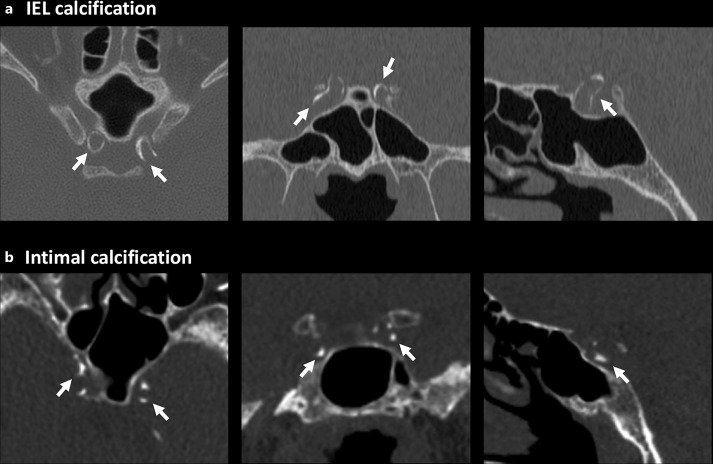

Methods: This cohort study used data from the National Taiwan University Hospital's pre-end-stage renal disease care database, including 2,622 CKD patients with brain CT scans from 2006 to 2020. Intracranial carotid artery calcifications were categorized as intimal or internal elastic lamina (IEL) subtypes. Multivariable Cox regression assessed the associations between each calcification subtype and incident stroke or vascular mortality.

Abstract Image